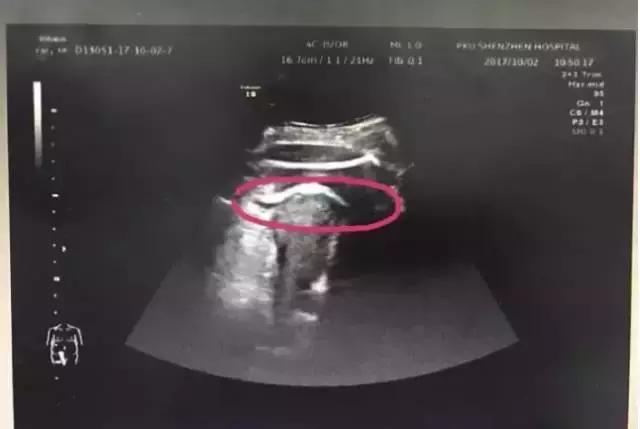

医生初步怀疑患者子宫破裂,当即安排做了B超。检查发现,胎儿的一条腿“踢破”了子宫,进入了腹腔,大腿根正卡在子宫壁上!

▲红色圆圈处是胎儿的腿,已经伸到子宫壁外

医生追问患者病史,原来张女士2016年做过子宫肌瘤剔除术,术后半年就怀孕了。不到2分钟B超检查,仅凭有限病史,医生快速作出诊断:高度怀疑为疤痕子宫破裂。